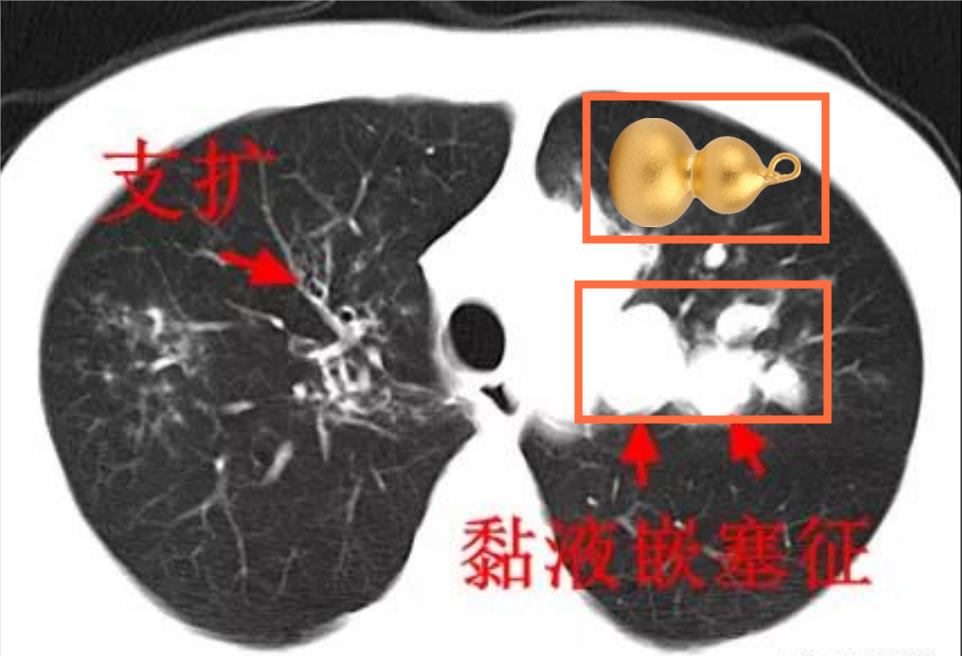

再看其 CT 片,支气管出现明显的葫芦状、指套状。

杨澄清立即联想到了一种常被忽视的真菌——烟曲霉,进一步进行检查发现,患者体内确实有烟曲霉特异性抗体。最终,根据对多项检查结果的综合评定,小勇被确诊变应性支气管肺曲霉病(英文简称 ABPA)。